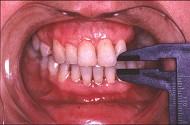

患儿,5岁,外伤后逐渐出现张口困难,咬合关系错乱,髁突动度减弱,外观及X 线检查结果如图。最可能的诊断是  (    )